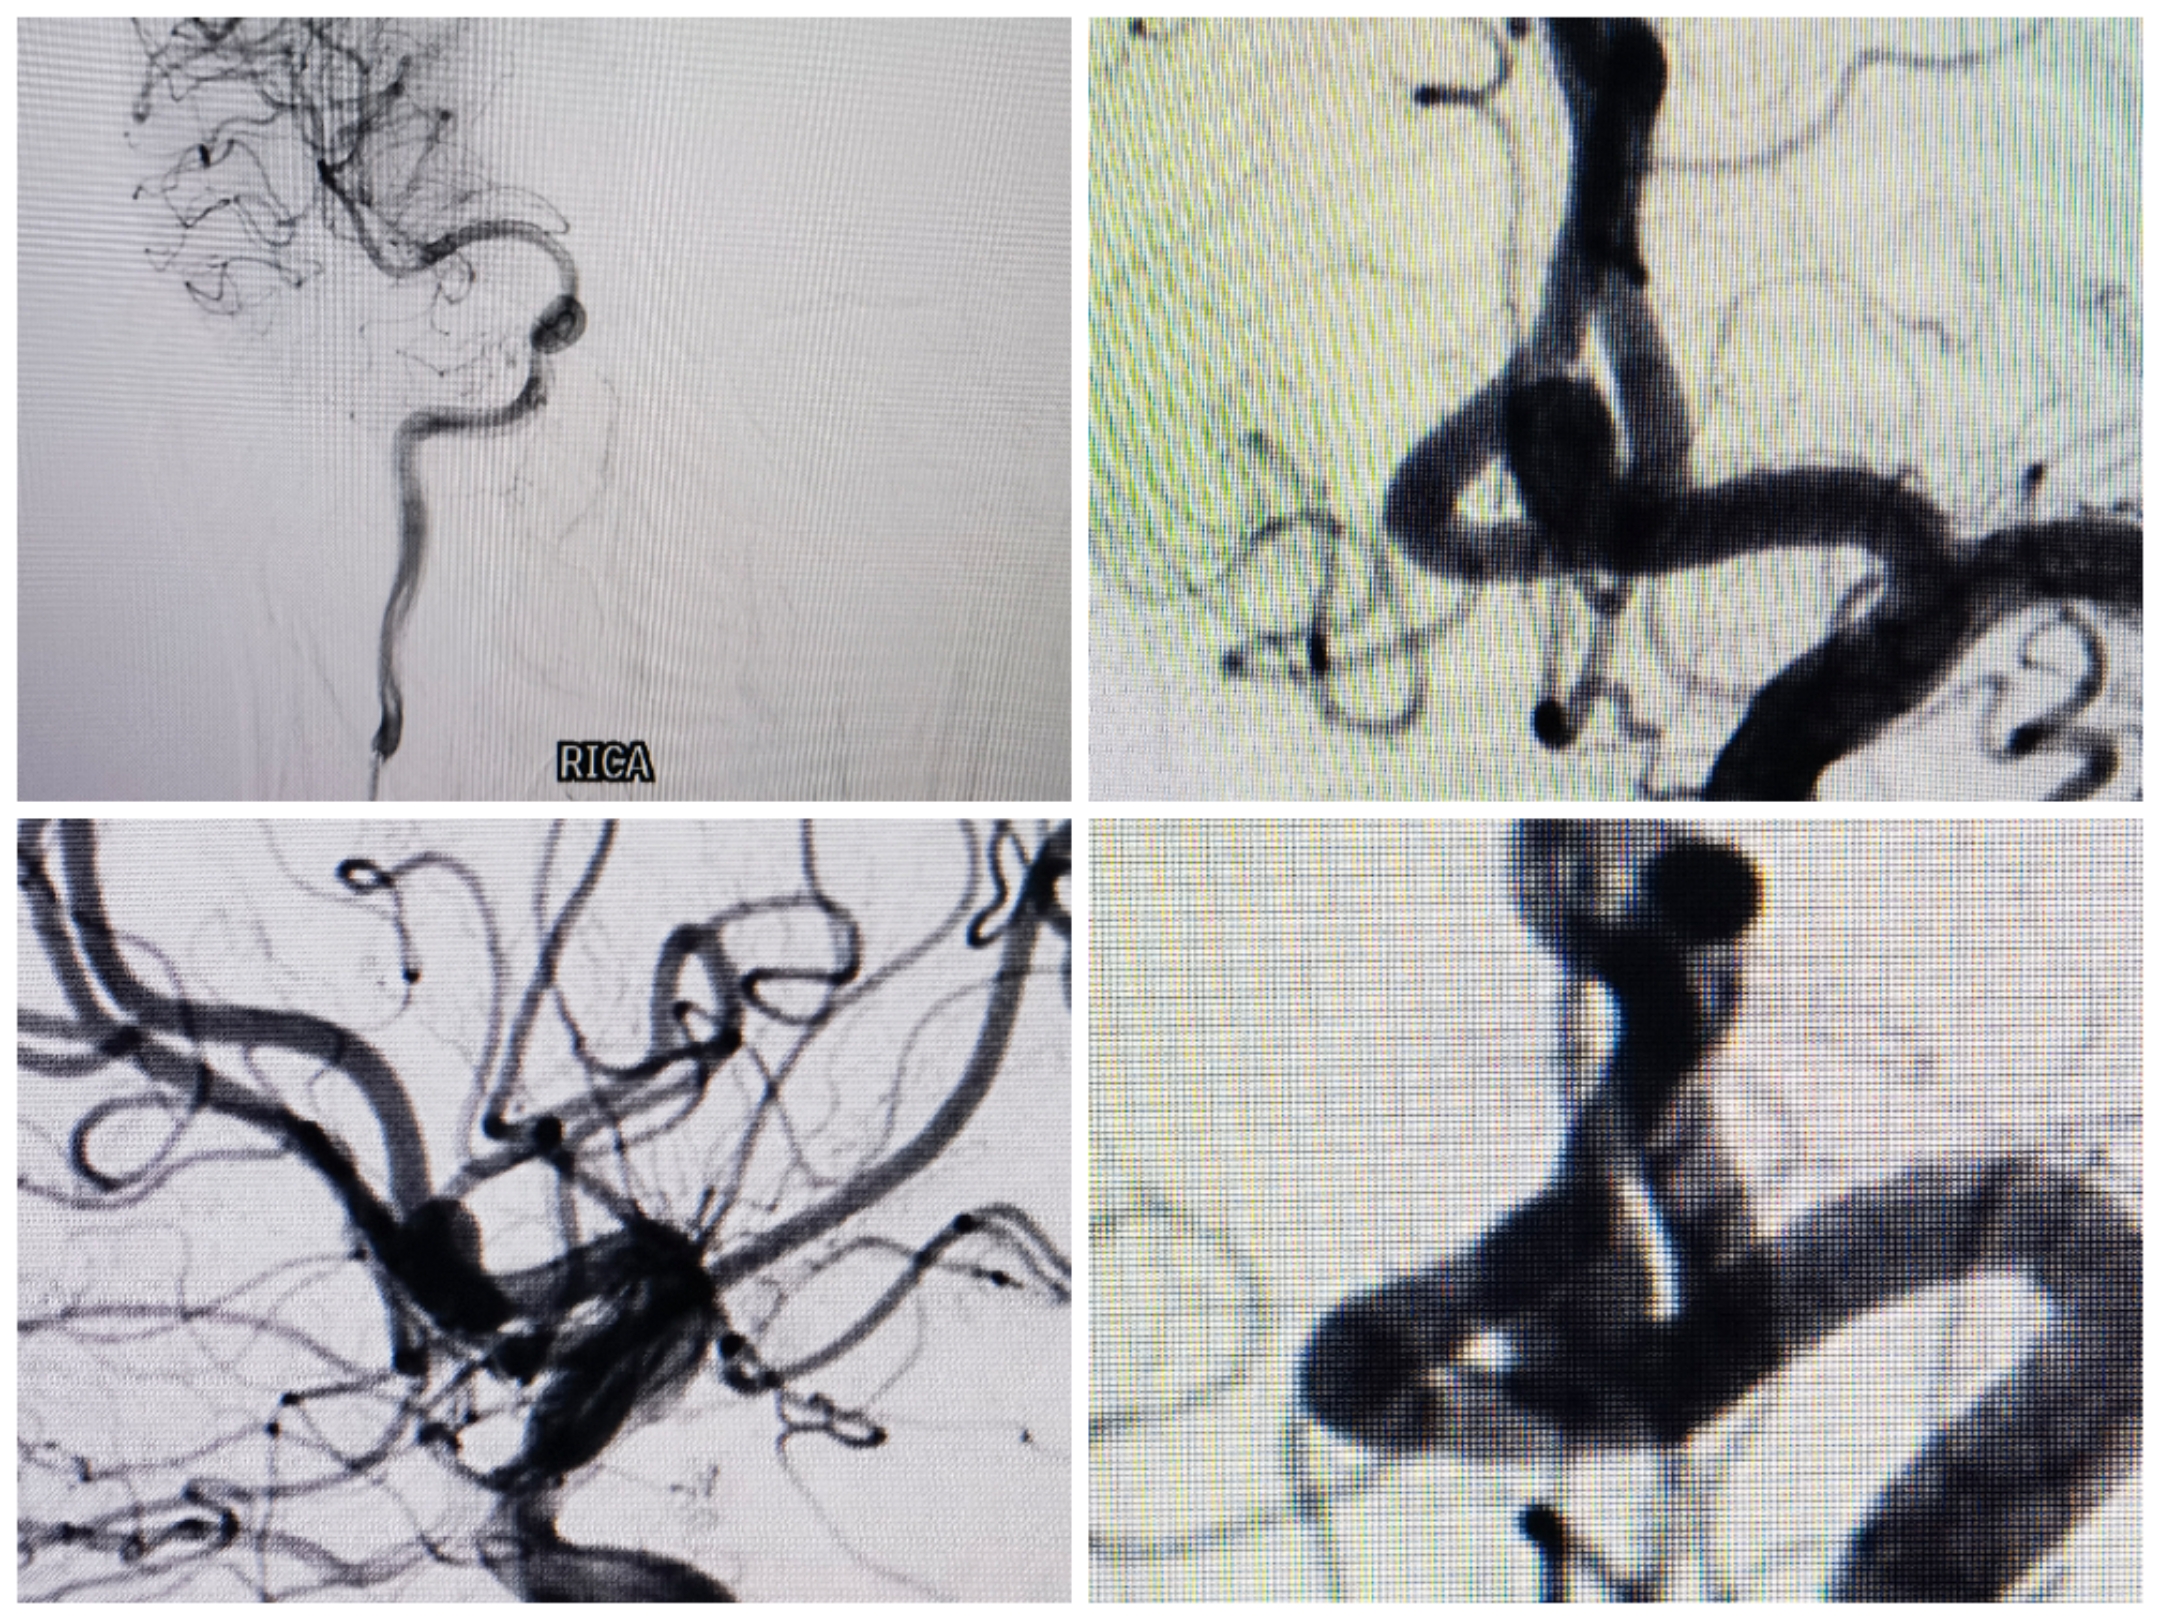

主动脉弓1型弓,右侧颈内:右侧大脑前A1存在

双椎造影无特殊

左侧颈内造影:前交通动脉瘤,窄颈

3D重建情况